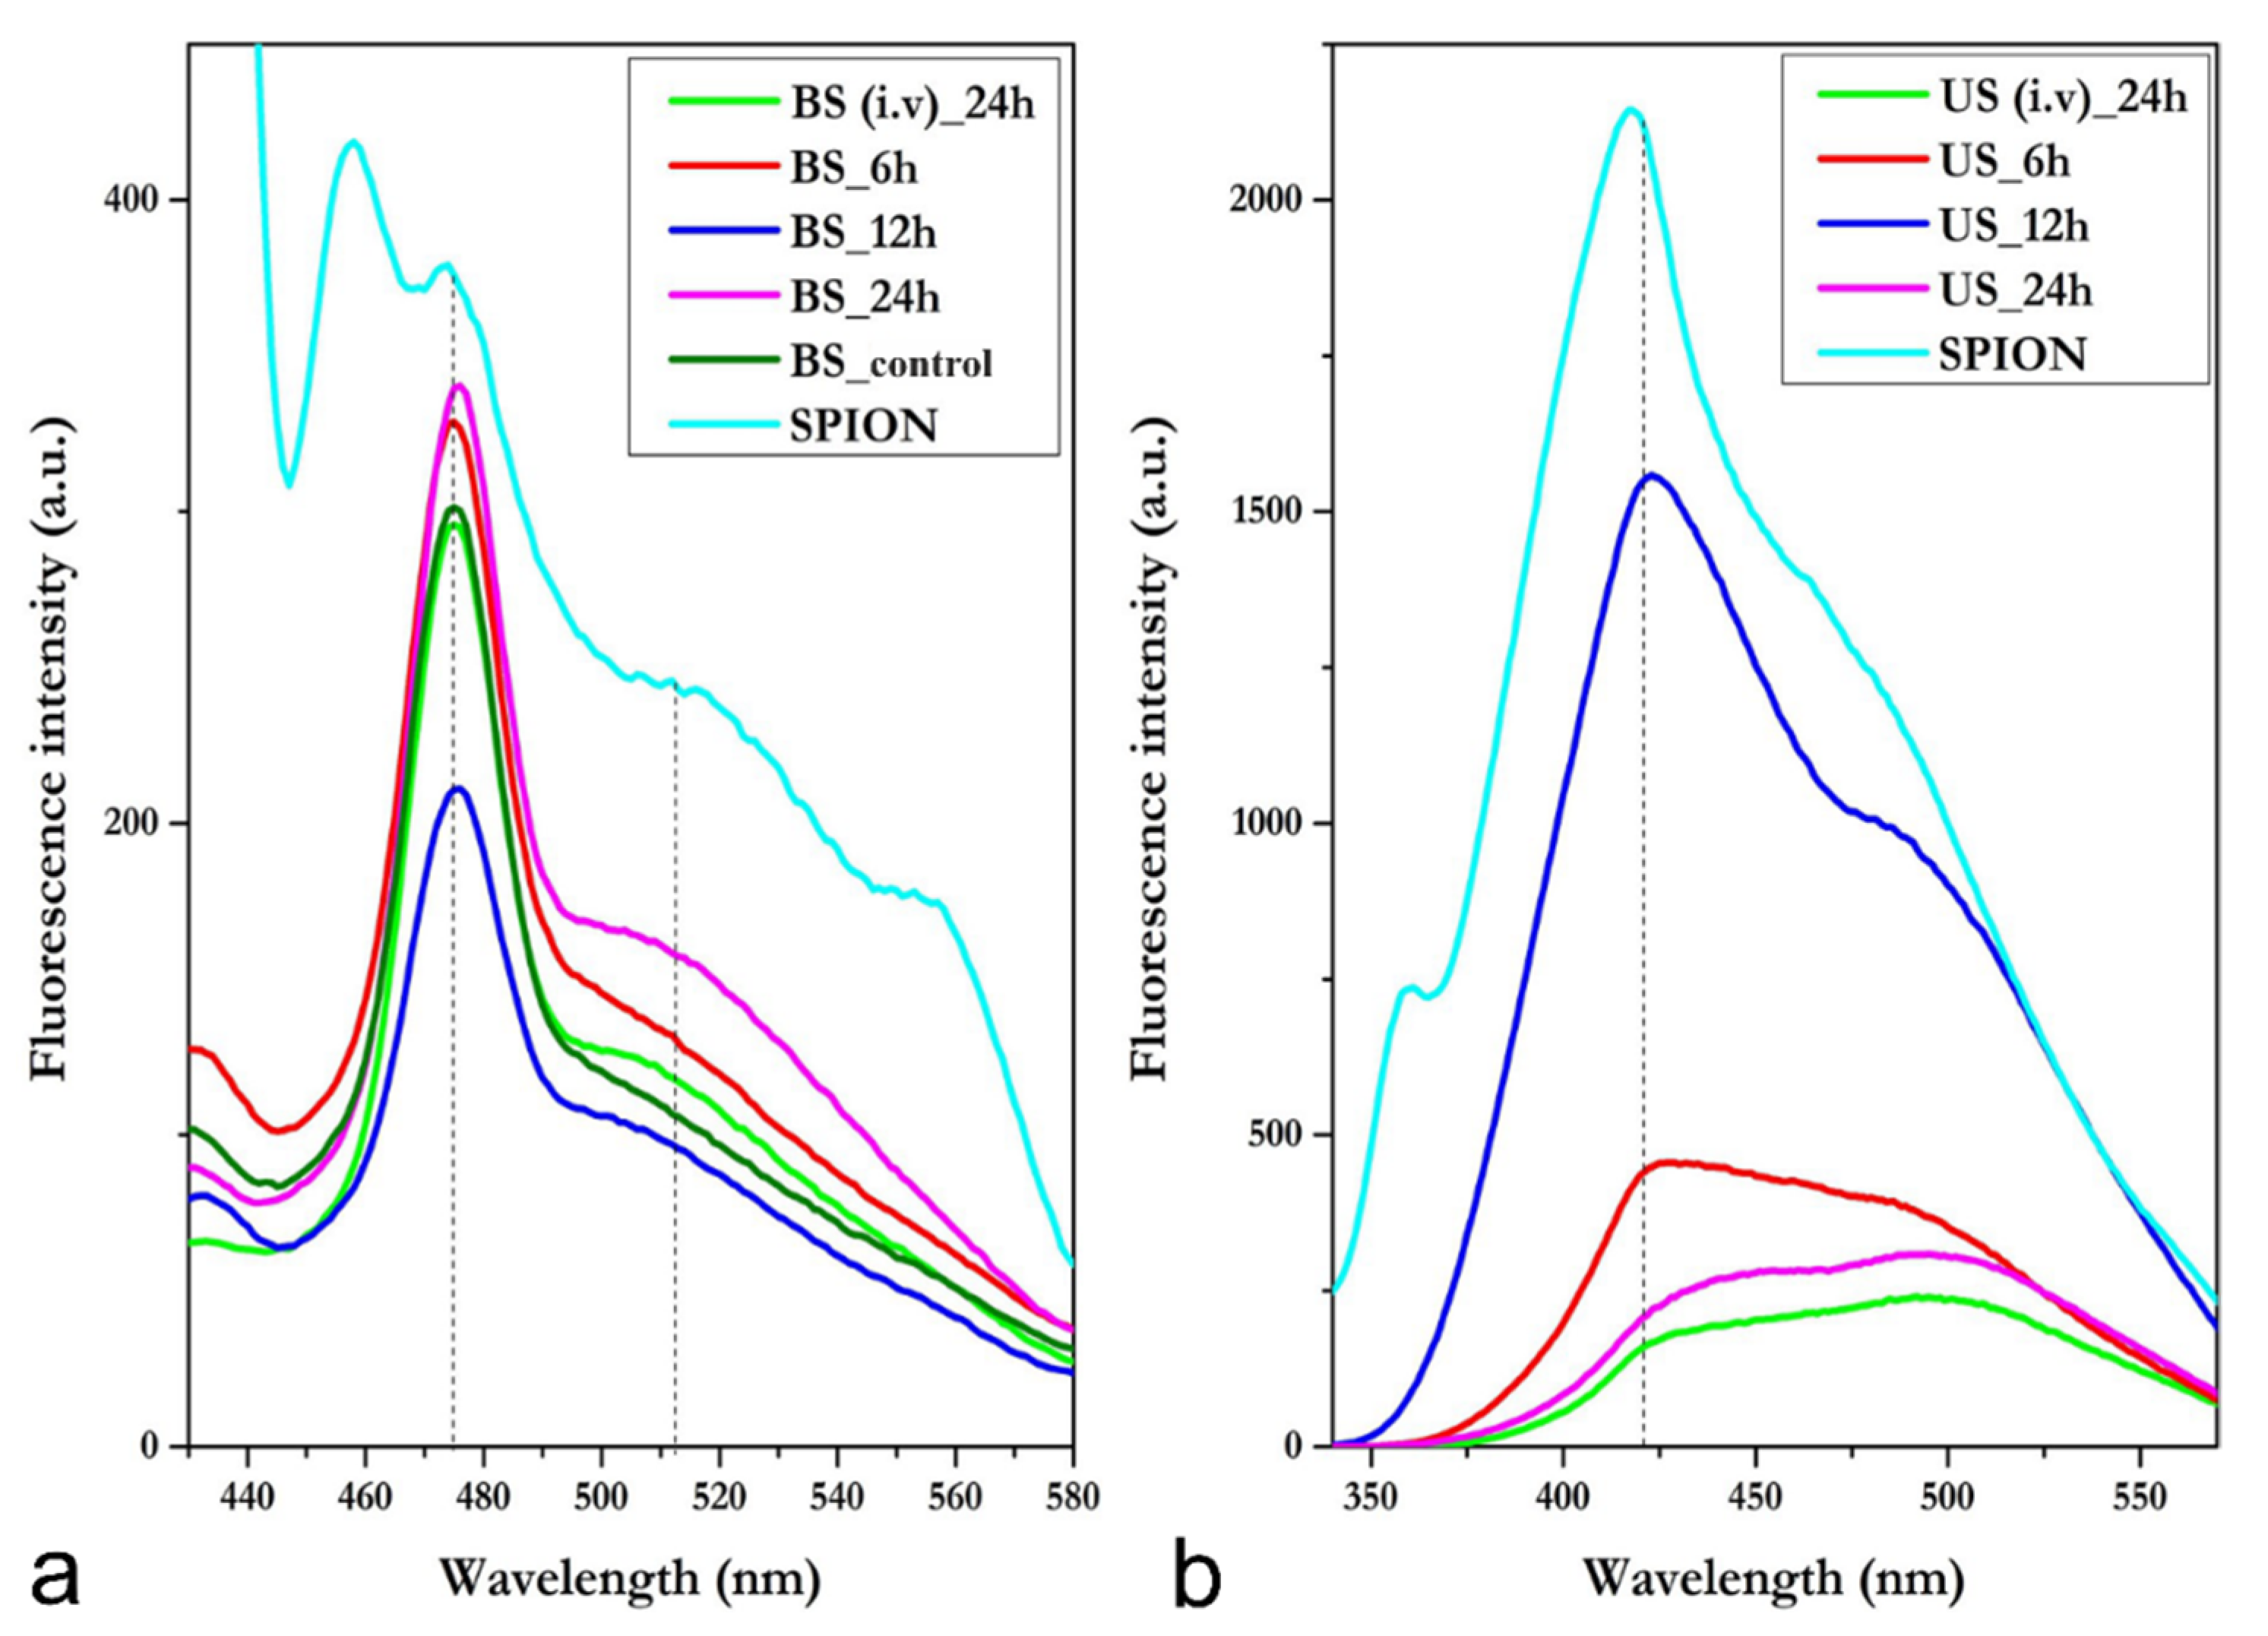

3.3. Blood Serum and Urine Spectrofluorimetric Studies

3.3.1. Blood Serum—i.p.

3.3.2. Blood Serum—i.v.

3.3.3. Urine—i.p.

3.3.4. Urine—i.v.